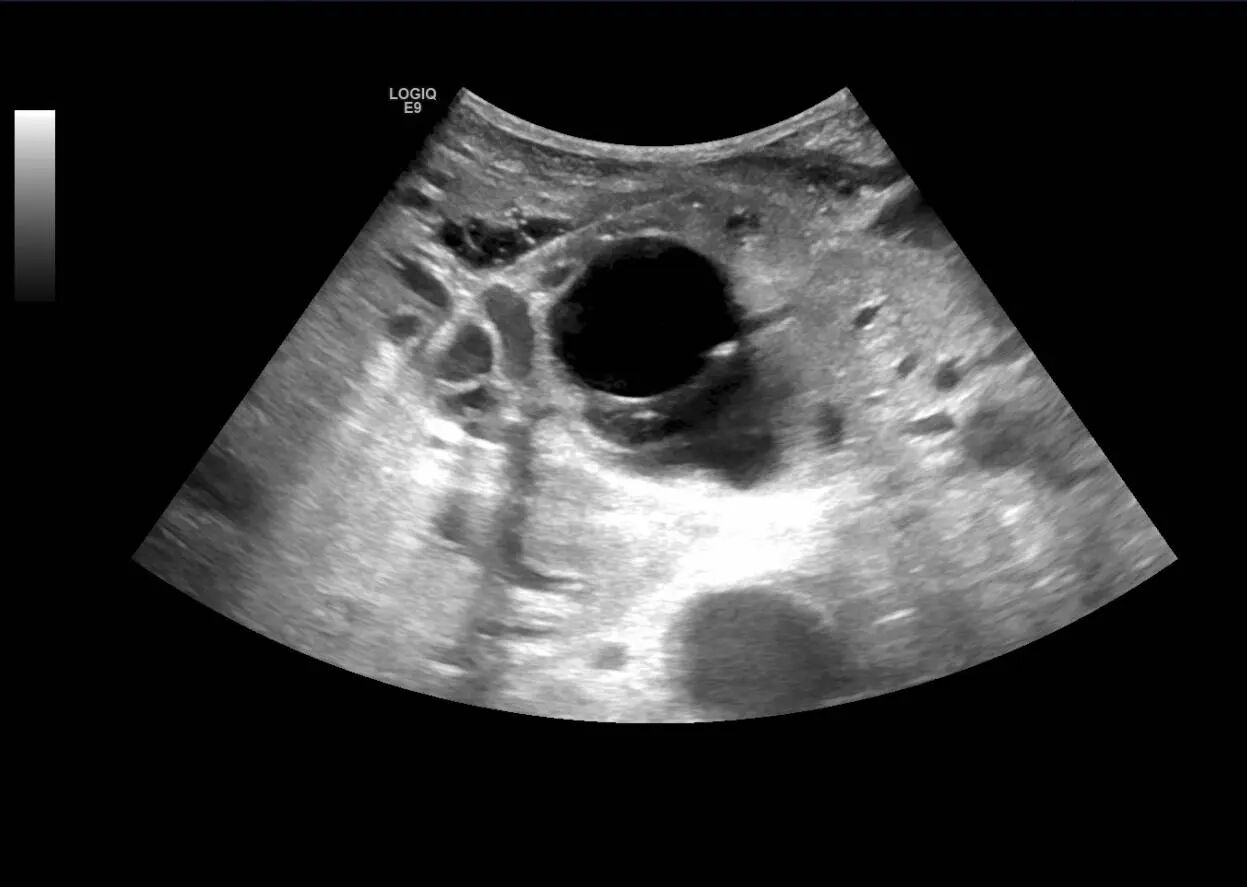

患者男性,70岁,9月下旬因腹胀腹痛1周、皮肤黄染就诊于我院综合外科。患者有结肠恶性肿瘤病史,身体虚弱,手术风险高。超声检查显示:患者肝内外胆管明显扩张,胆总管中下段占位,肝内转移瘤,需积极“减黄”,即黄疸治疗,以降低手术风险。

综合外科主任李前进与超声科主任罗利红综合评估后,拟行超声引导下经皮肝内胆管穿刺引流术(PTCD)。PTCD是在超声引导下,经皮肤及部分肝组织将穿刺针置入胆管内,再通过交换导丝将引流管置入胆道,疏通胆道、引流胆汁、缓解胆道梗阻,减轻黄疸腹痛等症状,达到改善肝功能之目的。